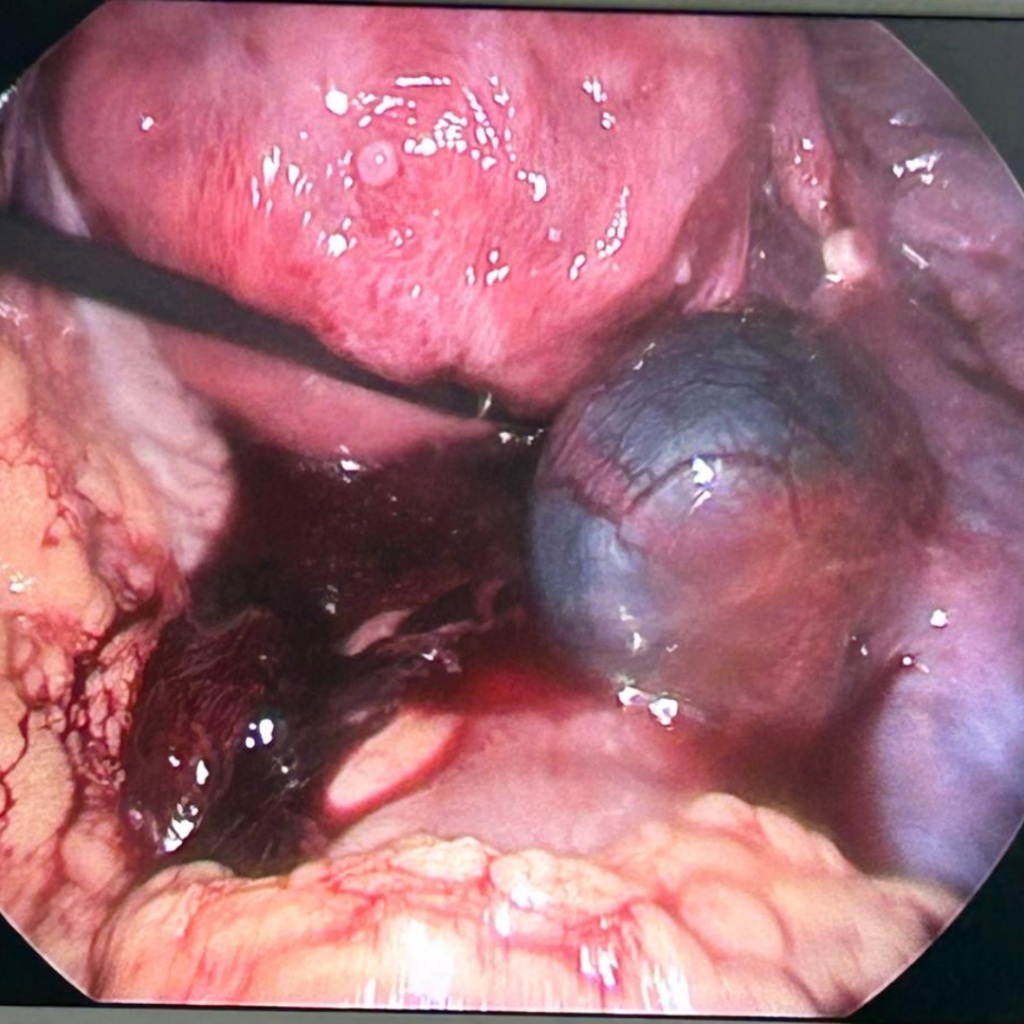

Laparoscopic clearance of ectopic pregnancy